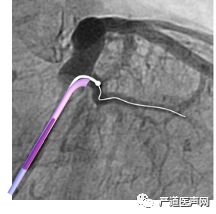

鞘中鞘经泥鳅导丝,通过瓣膜部位

鞘中鞘搭在靶静脉口

经鞘中鞘送左室导线进入侧静脉,张力大,左室导线前行困难

鞘中鞘前行支撑下仍无法进入

将鞘中鞘被再次送到靶静脉口支撑,由于分支太细,左室导线仍无法深入

调整左室导线,进入另一位置较高的分支

再次尝试PTCA导丝进入较高分支,左室导线顺利进入

讨论2-鞘中鞘的多种用途

常规用途:

在靶静脉与主干夹角成直角或锐角时,帮助找到靶静脉开口,并在开口处作为支撑,帮助左室导线植入。

本例用途:

冠状静脉窦瓣膜阻挡,电极导线无法进入冠状窦远端。如此时泥鳅导丝可进到远端,可先用使用鞘中鞘通过瓣膜部位,再通过鞘中鞘送入导线。